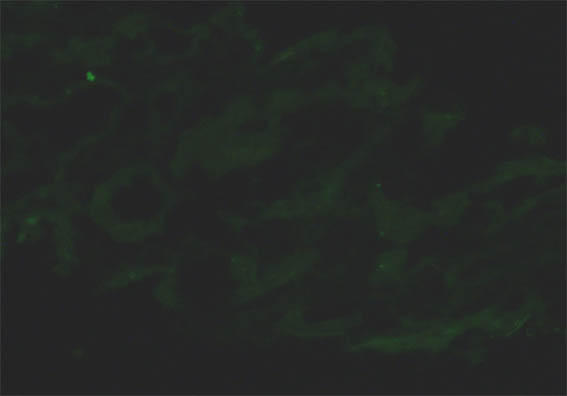

Inmunofluorescencia para cadenas ligeras kappa, X400.

Figura 8.

Inmunofluorescencia para cadenas ligeras lambda,

X400.